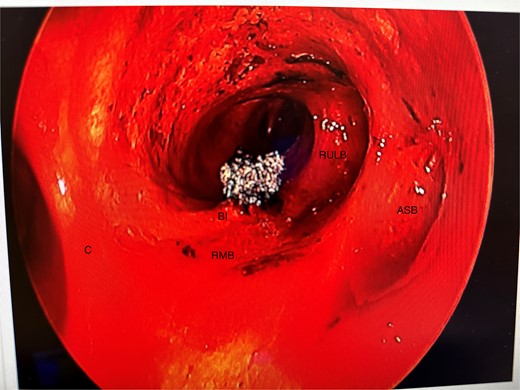

Anomalous right bronchial anatomy was also noted (Fig. 3). The biopsy was sent for frozen section, which confirmed a carcinoid tumour.

Post disobliteration of the tumour through rigid bronchoscopy, also showing aberrant anatomy, where the apical segmental bronchus of the right upper lobe has a high take off at the distal trachea/carina; C, carina; RMB, right main bronchus; BI bronchus intermedius; RULB, right upper lobe bronchus; ASB, apical segmental bronchus.